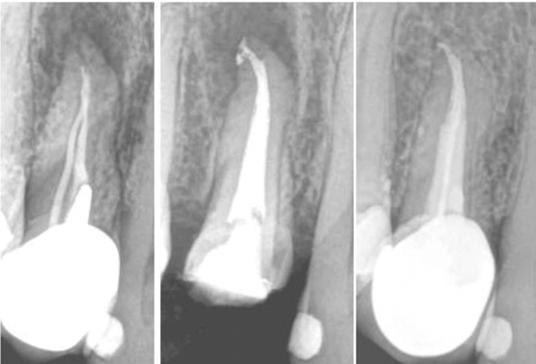

Clinical case performed by Dr. Sameer Jain (Figures 6 and 7)

The RCT involved a deep split tri-furcated premolar. Use of Odne®Clean enabled access to the advanced canal anatomy.

Figures 4 and 5: Clinical case performed by Dr. Brett Gilbert

Figures 6 and 7: Clinical case performed by Dr. Sameer Jain